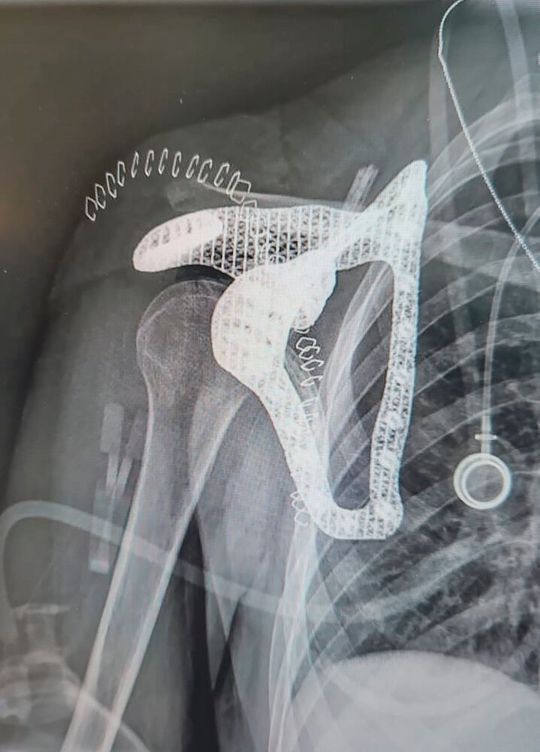

A team of experts jointly developed a titanium scapula implant that is precisely tailored to the patient's anatomy.(Image: Tel Aviv Medical Center)

A team of experts jointly developed a titanium scapula implant that is precisely tailored to the patient's anatomy.

In a joint project, a team of experts from the Tel Aviv Medical Center, PTC, and Hexagon created a fully patient-specific scapula implant for a 16-year-old cancer patient. The team used additive manufacturing and medical imaging to design and manufacture a titanium scapula implant precisely tailored to the patient's anatomy.

The experts performed a 3D segmentation of the tumor and the surrounding bone to enable effective reconstruction. A digital twin of the anatomical model was created and printed at a 1:1 scale to support preoperative planning and delineate the resection margins. At the same time, a custom 3D-printed implant was designed with PTC's CAD software Creo to anchor the remaining muscle stumps and reconstruct the joints.